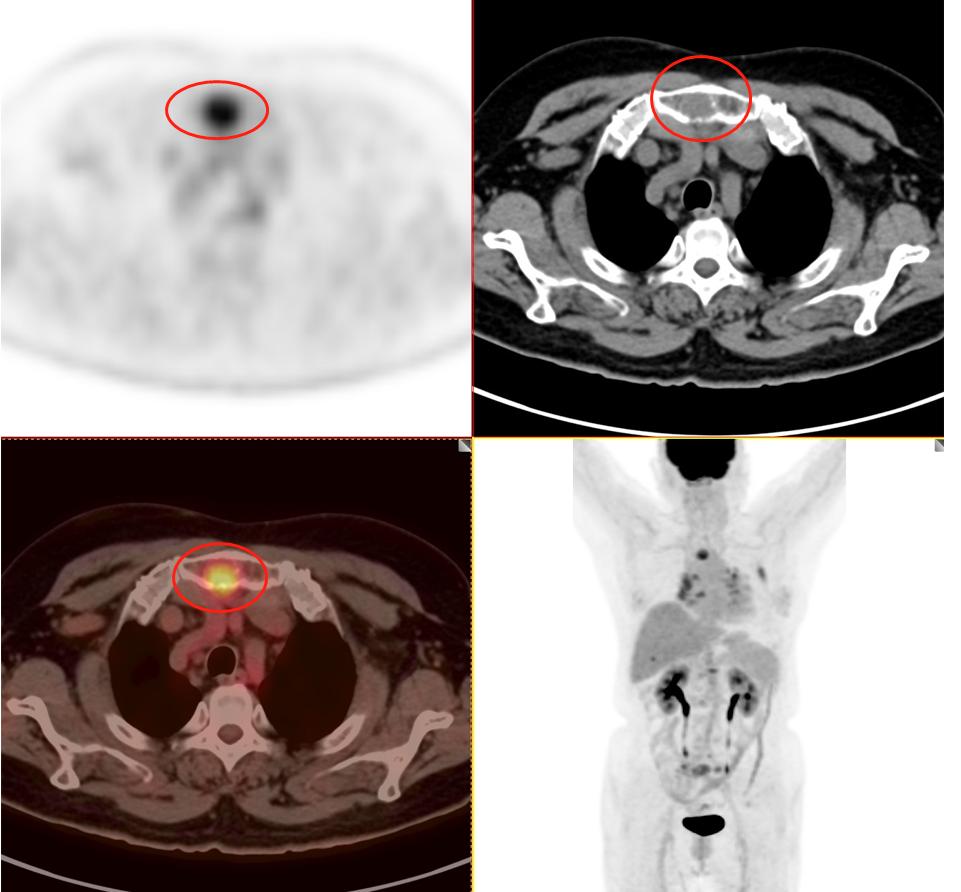

患者2:图3

发现纵隔多发淋巴结转移,并转移到对侧纵隔。